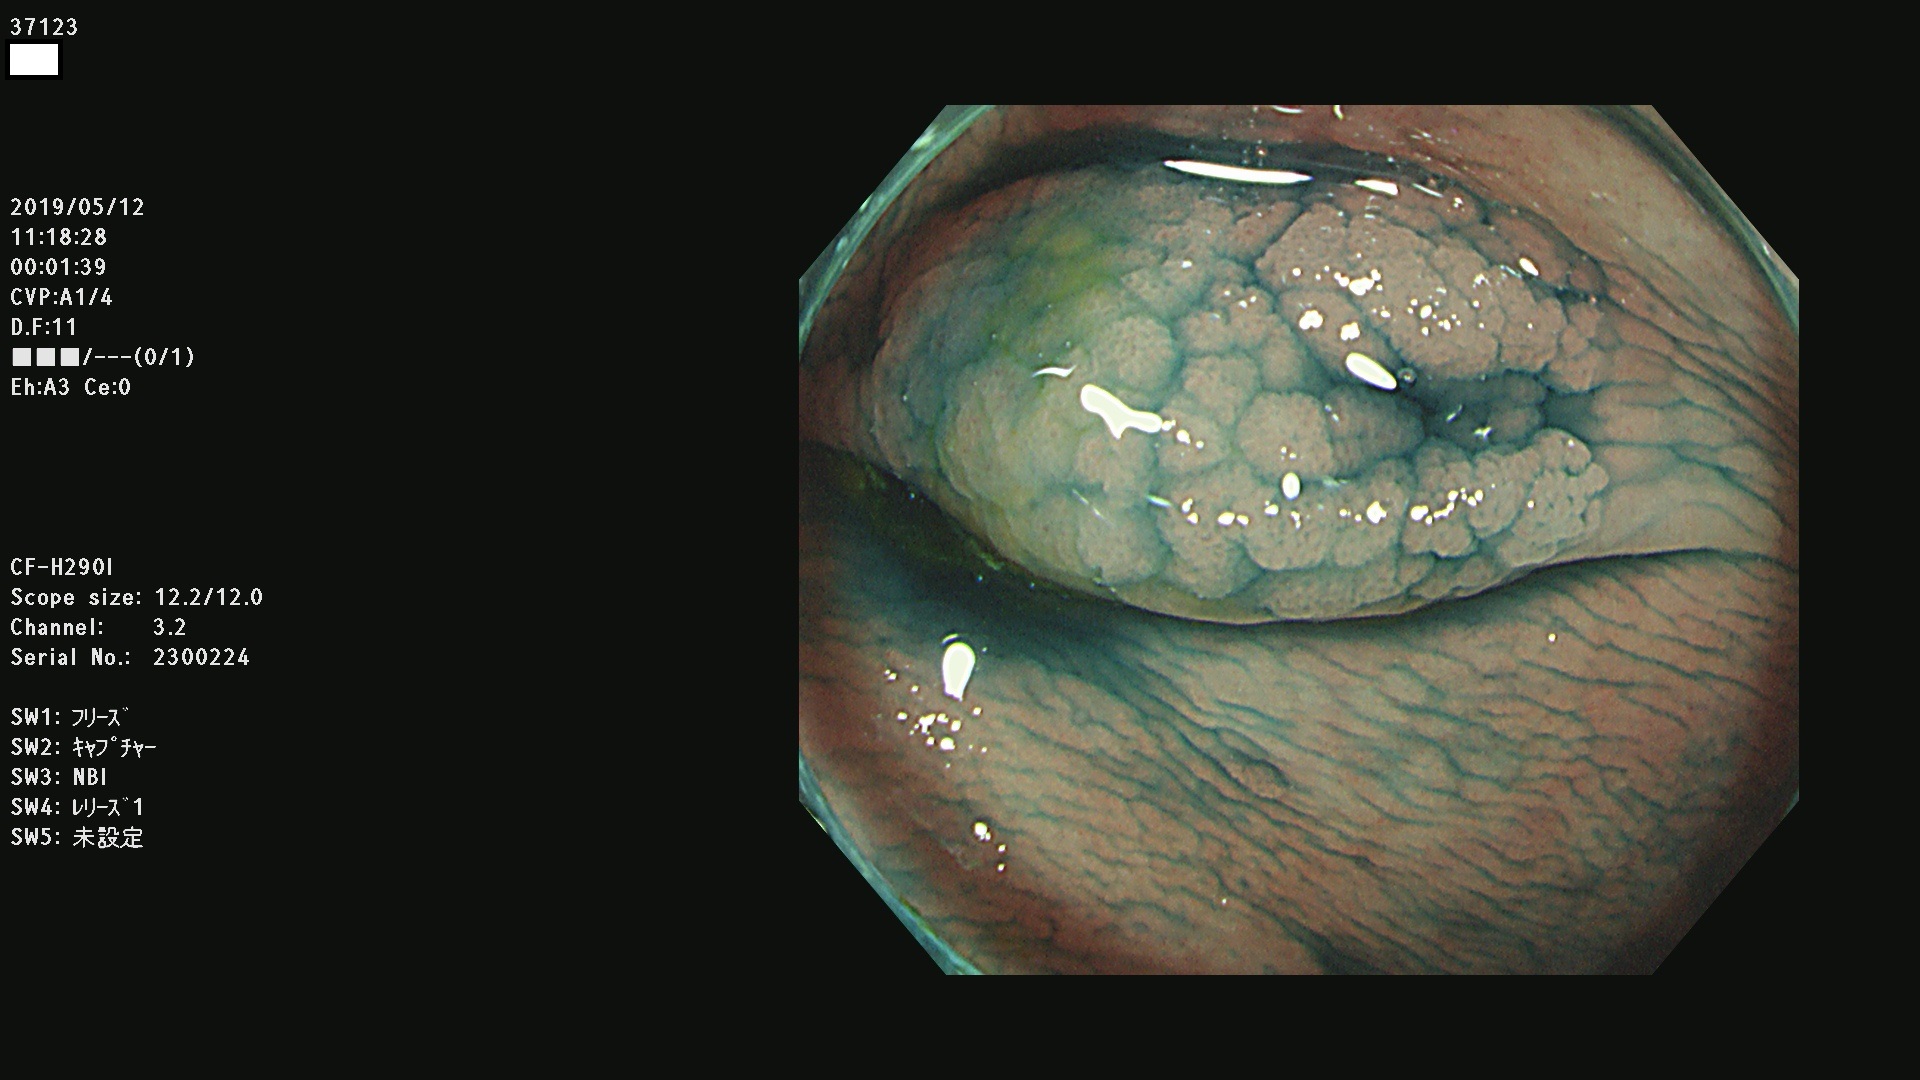

37100 37101 37102 37104 37106 37108 37110 37111 37112 37113 37115 37118(SSAPのみ) 37120 37122 37123 37124 37127(SSAPのみ) 37128(SSAPのみ) 37131 37132 37133 37134 37135 37139 37141 37142 37143 37144(SSAPのみ) 37145 37147(SSAPのみ) 37148 37149 37150 37153 37154 37157 37159 37161 37162 37163 37164 37165 37166 37167 37168 37169 37170 37171 37172 37173 37175(SSAPのみ) 37176 37177 37178 37180(SSAPのみ) 37181 37184 37185 37186 37187 37188 37189 37190 37192 37194 37197 37198

発見困難で危険性の高い平坦型病変(上記100名より抽出)